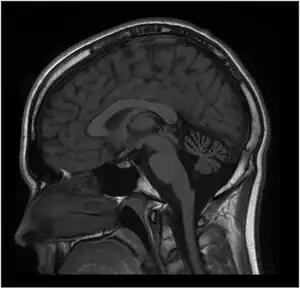

| MRI of the brain. MRI was performed on Person 1 at 12 years of age. T1W1 sagittal image demonstrates prominent cerebellar atrophy involving superior and middle cerebellar folia. Axial images (not shown) revealed normal subcortical and cerebellar white matter. MR spectroscopy was normal (not shown). Repeat MRI imaging at 16 years old was unchanged (not shown). MRI of the brain (Person 2) showed a similar pattern but milder cerebellar atrophy (not shown). | |